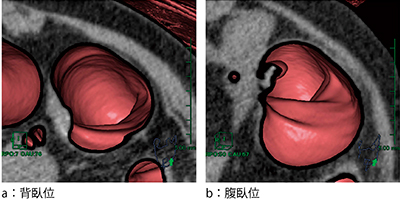

7.2体位比較読影でポリープ位置の記録(図6)

2体位比較読影でのポリープ位置の記録が大腸の長さに応じた位置に表示されるようになり,一目で両体位におけるポリープ位置が確認可能となった。ポリープの番号は,肛門側と直腸側のどちらからでも編集が可能となり,所見記載時に大変便利となった。

図6 2体位比較読影におけるポリープ位置の記録